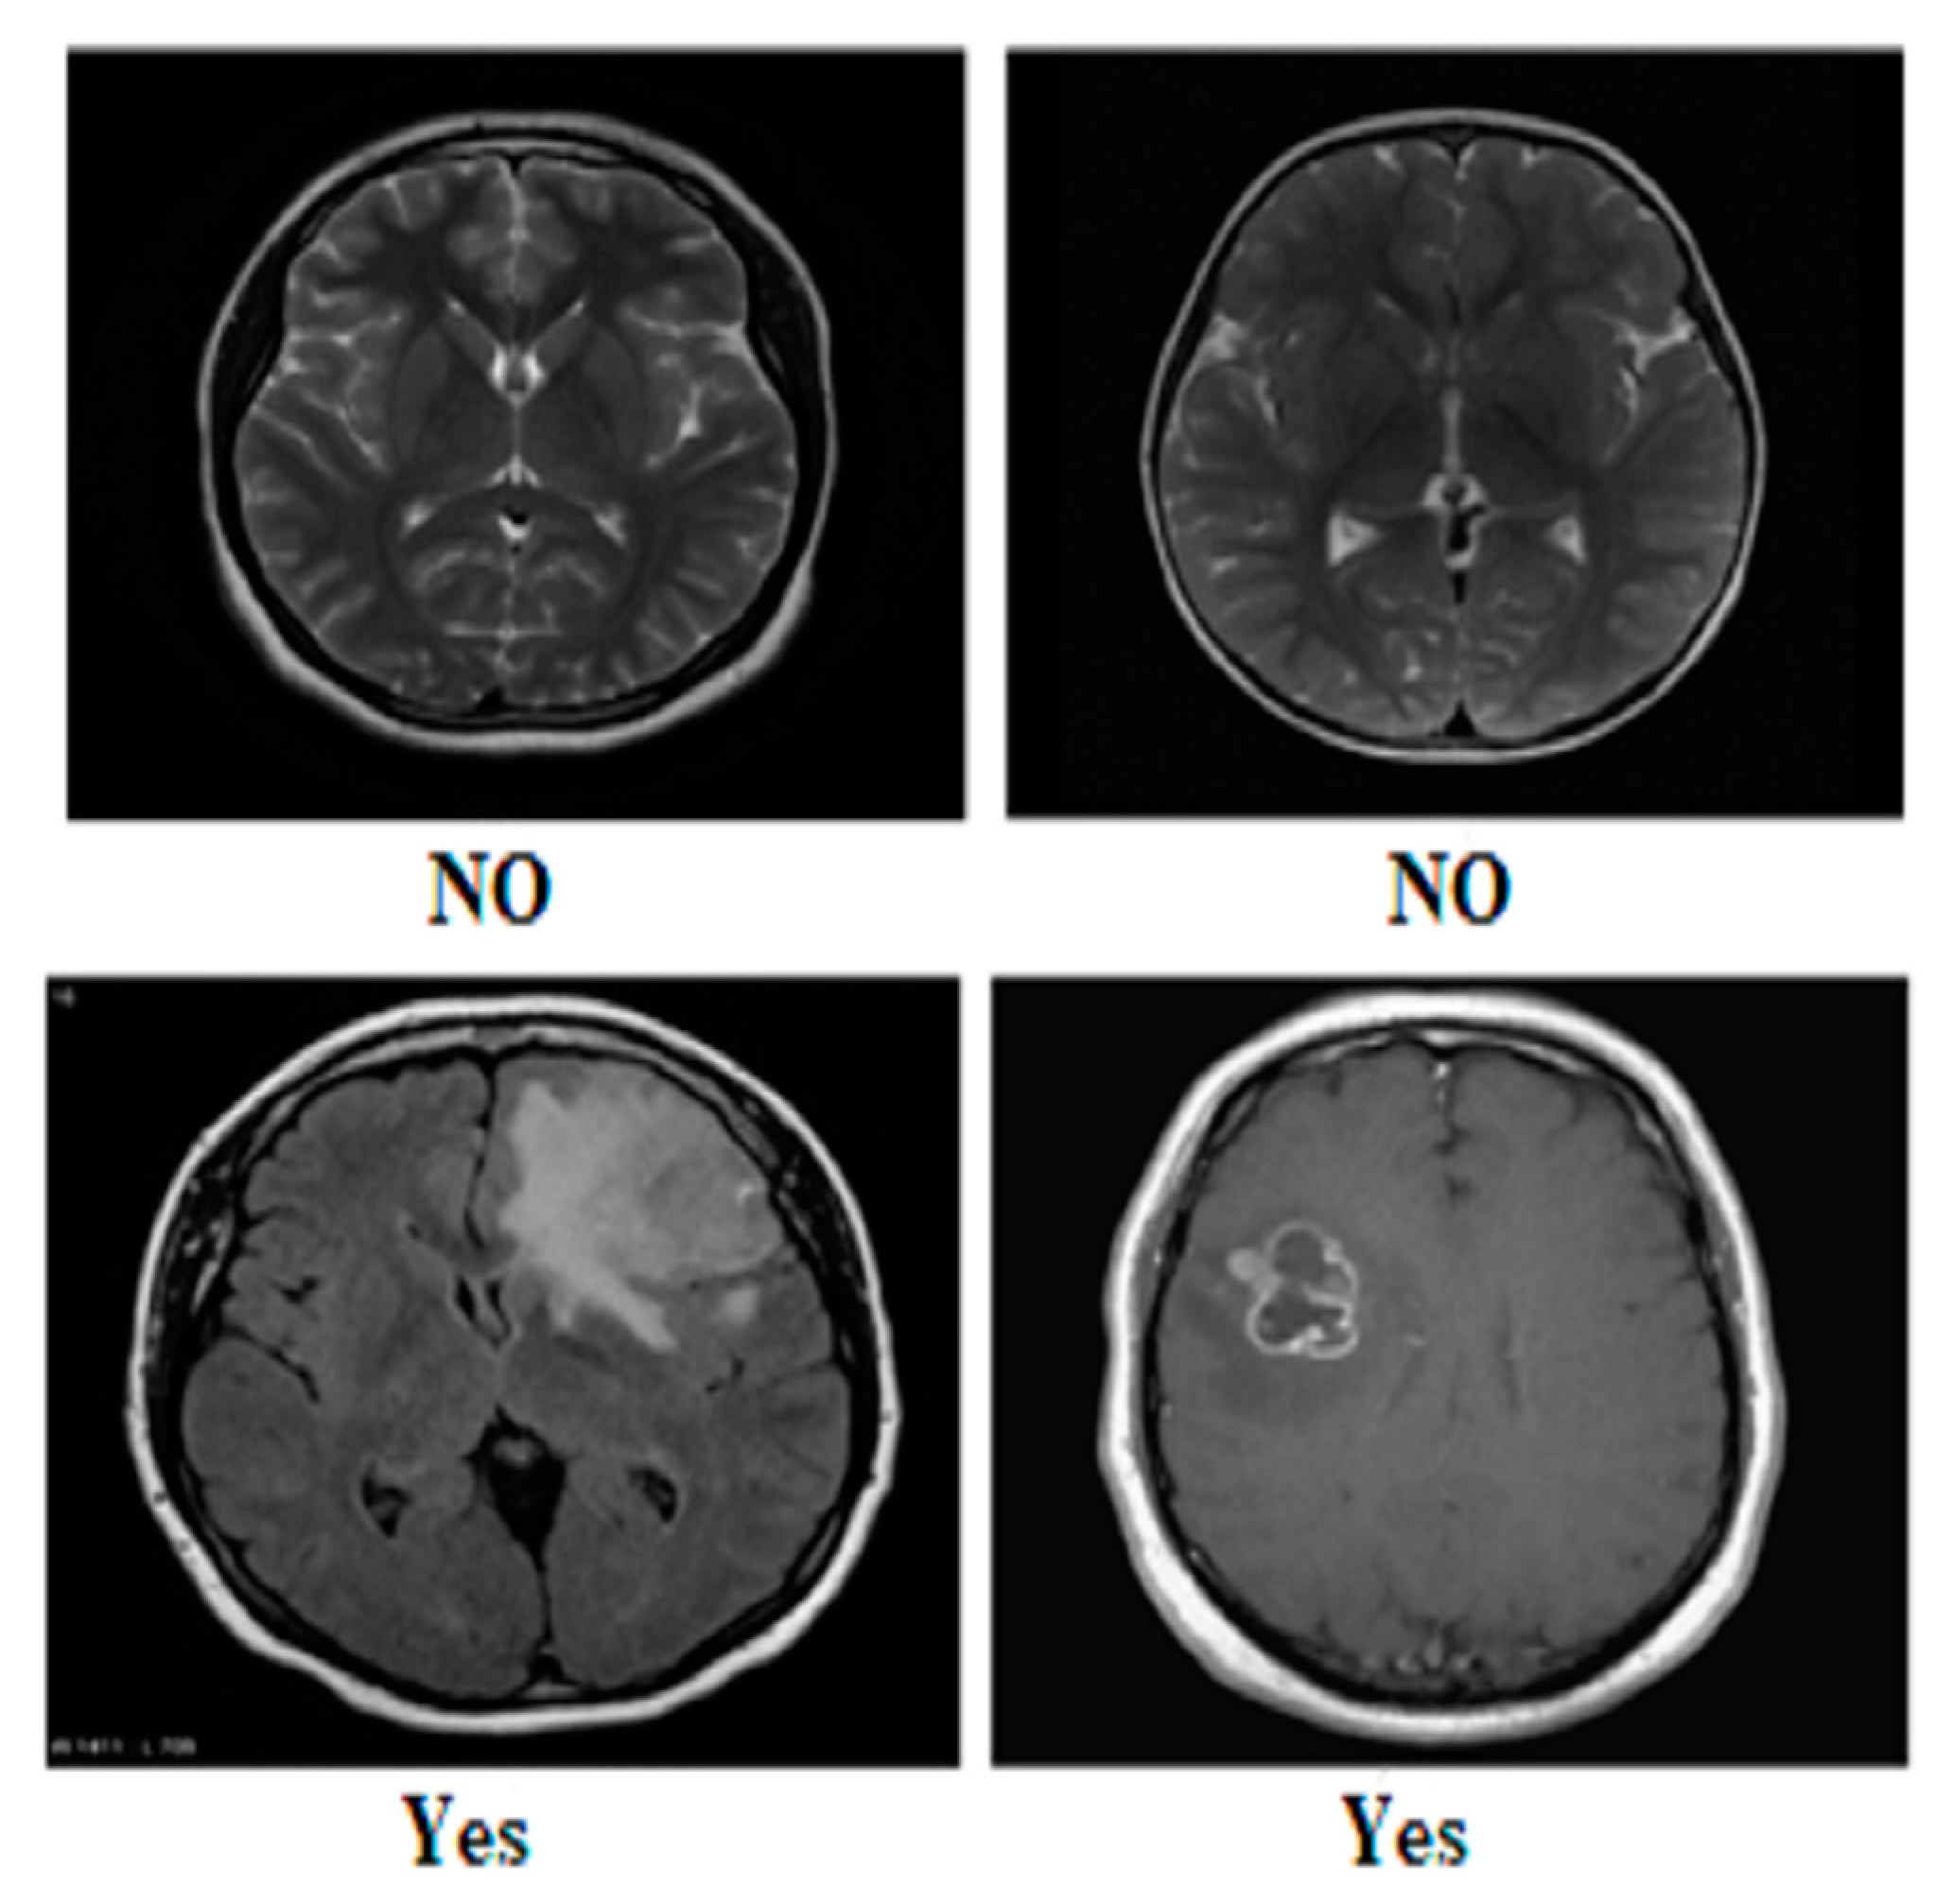

| Glioma | 1621 | 1321 | 300 | Yes | 155 | 135 | 20 | Yes | 1500 | 1200 | 300 |

| Meningioma | 1645 | 1339 | 306 | No | 84 | 66 | 18 | No | 1500 | 1200 | 300 |

| Pituitary | 1757 | 1457 | 300 | ||||||||

| No Tumor | 2000 | 1595 | 405 | ||||||||

| Total | 7023 | 5712 | 1311 | Total | 239 | 201 | 38 | Total | 3000 | 2400 | 600 |